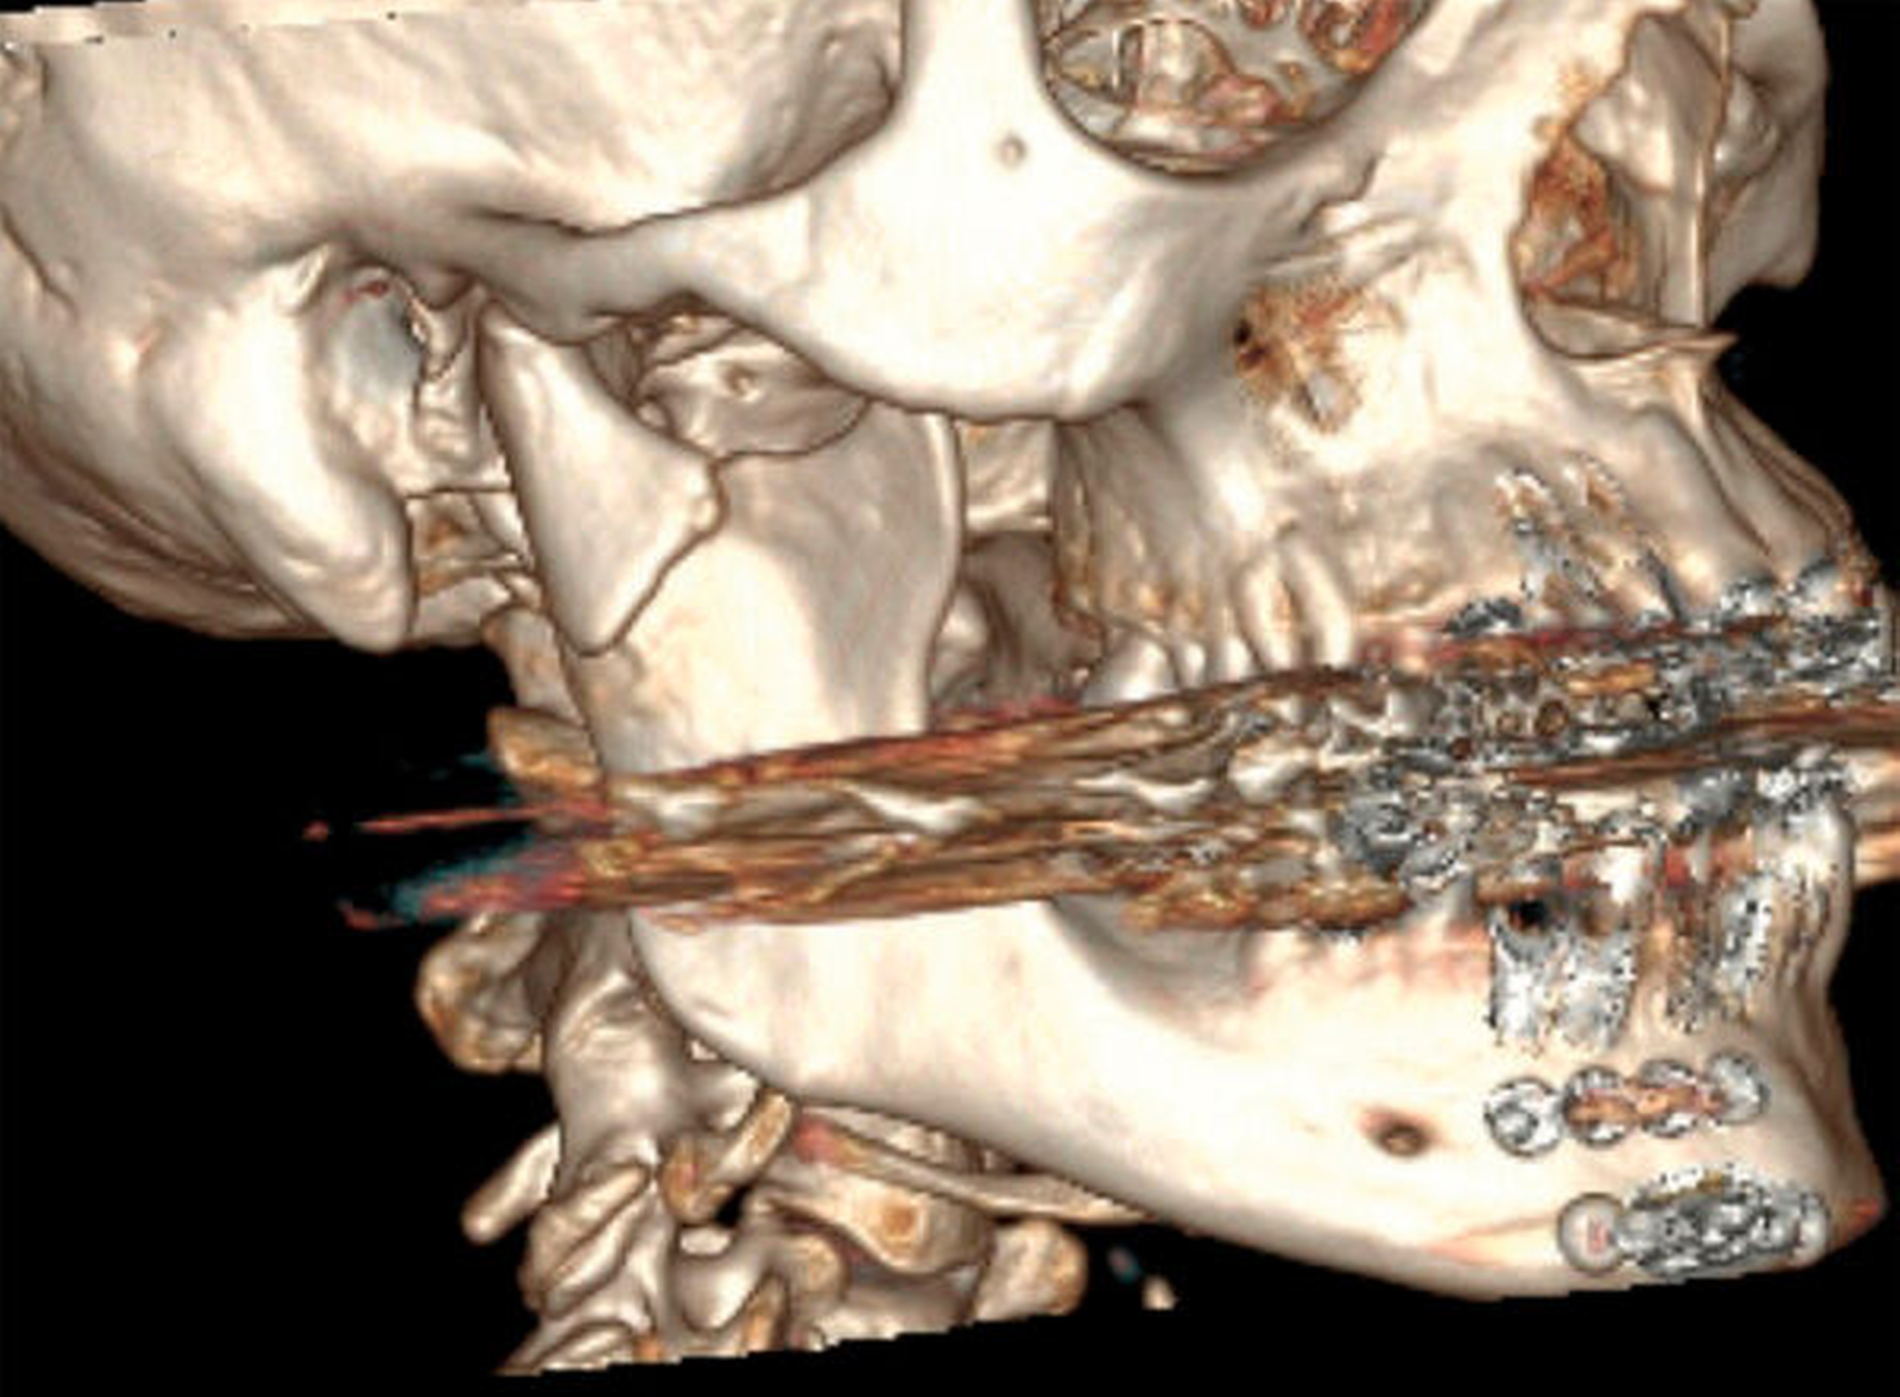

Die Patientin war sehr verängstigt, da sich die Situation immer weiter verschlechterte, ihr Biss sich also immer mehr verschob. Insbesondere beklagte sie die kaufunktionelle Einschränkung mit dem Unvermögen des Abbeißens, aber auch den für sie ästhetisch unbefriedigenden Status. Sensorische oder motorische Defizite lagen nicht vor. Eine 3-D-radiologische Untersuchung via dentaler Volumentomografie (DVT) zeigte beidseits in Fehlstellung teilweise pseudarthrotisch eingeheilte Kiefergelenksfortsätze sowie eine suffiziente osteosynthestische Versorgung paramedian rechts (Abbildungen 2 und 3).

Auch unter Beachtung des langen Zeitraums zwischen dem Frakturhergang und der Vorstellung wurden mit der Patientin die Optionen des Belassens der Situation, einer kieferorthopädischen, einer prothetischen und einer chirurgischen Therapie mit den jeweiligen Vor- und Nachteilen ausführlich besprochen. Sie entschied sich für die chirurgische Option, da sie sich hierdurch am schnellsten Besserung erhoffte. Daher erfolgte im Rahmen einer Intubationsnarkose die Darstellung der beiden in Fehlstellung verheilten Frakturen über einen präaurikulären Zugang (Abbildung 4). Mittels Piezochirurgie folgte die Re-Osteotomie im Bereich der ehemaligen Brüche. Eine intermaxilläre Fixierung durch Drahtligaturen und IMF-Schrauben ermöglichte anschließend eine funktionsstabile Osteosynthese mittels Miniplatten in Okklusion (Abbildungen 5 und 6).